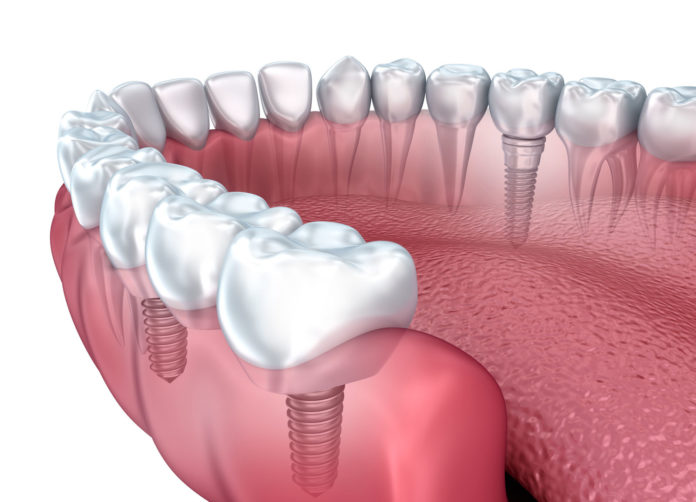

Dental implant restoration may look like the natural tooth because it easily fuses into your jawbone. As compared to dentures, the dental implants are preferred as they help you chew your food better. It also provides better strength to bite into food with no change in taste or sense of smell.

Whenever you lost a tooth, one of the most used teeth replacement options was to have a dental bridge. And quite often, this would involve cutting off some parts of adjacent healthy teeth so that there is a proper balance of the dental bridge. But with dental implants, a crown or a bridge on the dental implant can be easily positioned. And the other teeth also do not need to suffer due to the plight of one tooth.